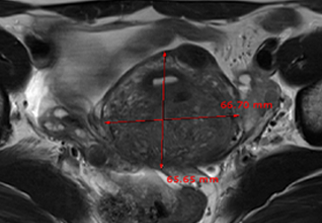

자궁근종 비수술 하이푸 치료 후 임신분만사례입니다. 아직 자녀가 없으신 분으로 복부에 만져지는 증상으로 자궁근종 하이푸 치료를 위해 내원하였습니다. 하이푸 시술전 MRI 사진상 자궁은 7.5cm 크기로 자궁전벽의 ...